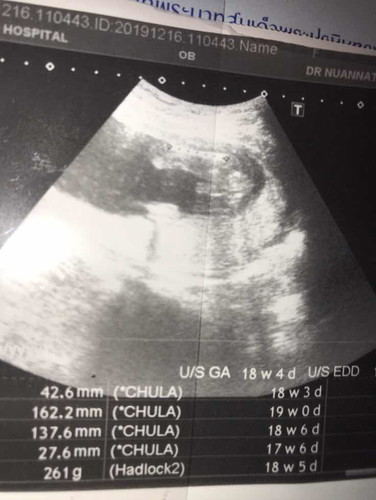

เพศลูก

แม่ๆดูออกมั้ยค่ะว่าเพศอะไร??❤️

เหมือนจะเห็นอะไรยื่นๆน่าจะผู้ชายค่ะ